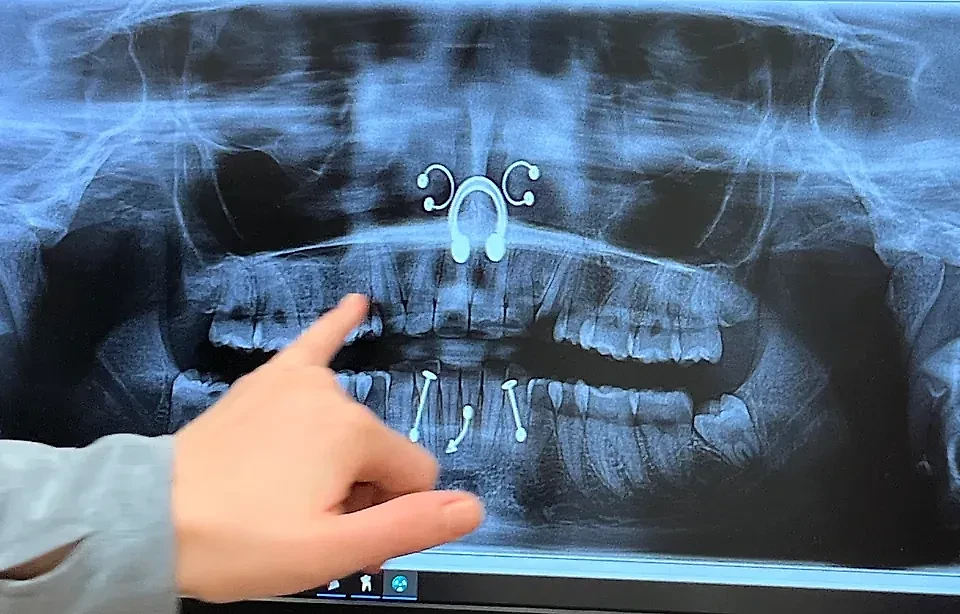

"Пришла на консультацию по поводу моих зубов мудрости. Мне разрешили не снимать пирсинг", — dist0rtе.

Фото © Reddit / dist0rte